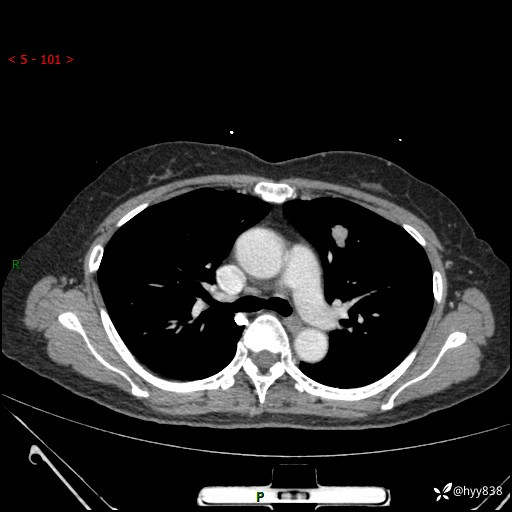

54岁/女,发现肺占位1天。观其形态和强化,术前我信心十足,术后我---结果公布~

【患者信息】:54岁/女

【主诉】:发现肺占位1天

【现病史及既往史】:患者2023.10.23体检发现肺占位:,2023.10.23当地区中心卫生院胸腹部CT:1.左肺上叶结节,考虑为占位可能;2.肝脏小囊肿灶;3.子宫左侧附件区畸胎瘤;无咳嗽咳痰,无恶心呕吐,无发热,无胸闷胸痛等不适;现患者为求进一步诊治来我院,门诊以“肺占位”收入我科。 患者自起病以来,精神饮食睡眠一般,大小便正常,体力体重无明显下降。

【检查】:胸部CT增强(外院平扫)